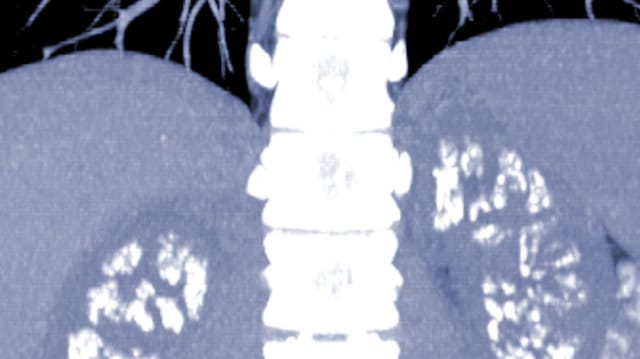

Die sehr seltene Krankheit «Primäre Hyperoxalurie Typ 1» (PH1) ist eine genetisch bedingte Stoffwechselkrankheit, die auf den Ausfall eines Enzyms zum Abbau von Fettsäuren zurückgeht. Durch eine hohe Konzentration von Oxalsäure in Verbindung mit Calcium kommt es in der Niere – und anderen Organen – zur Bildung von Calciumoxalsäure-Kristallen (Nierensteinen).

Diese können die Nierenfunktion vermindern und zu einer Niereninsuffizienz bis hin zum Ausfall der Nierenfunktion führen. PH1 tritt in vielen unterschiedlichen Formen in unterschiedlichen Altersgruppen auf und gilt als deutlich «unterdiagnostiziert». Studien schätzen die Häufigkeit von PH1 auf etwa eine betroffene Person pro 150 000 Einwohner. Bisher bestand die einzige Kausaltherapie in einer Lebertransplantation.